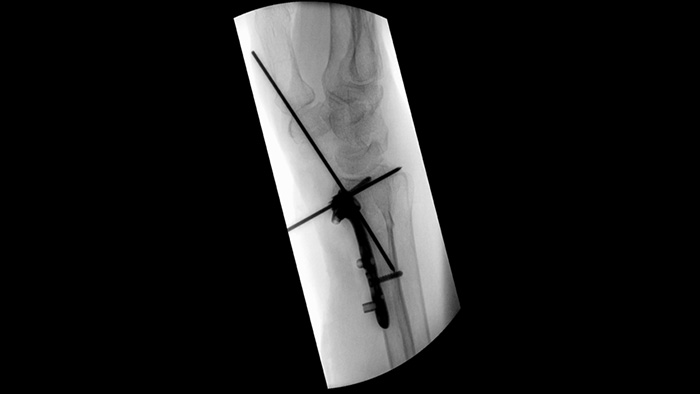

Simplifique el flujo de trabajo para casos desafiantes de ortopedia que requieran el reposicionamiento frecuente del arco de quirófano. Con la memoria de posición2, los participantes en un estudio de facilidad de uso1 lograron el 94% de reposicionamiento correcto en el primer intento y experimentaron menos frustración durante las tareas de reposicionamiento.

Los obturadores asimétricos únicos aumentan la flexibilidad de la colimación y ayudan a colimar la anatomía mediante la colocación independiente del obturador con la punta de los dedos. Puede ajustar los obturadores y la orientación de la imagen mientras está en la posición de la última imagen en pantalla sin utilizar radiación.